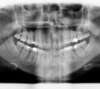

Radios avant le traitement